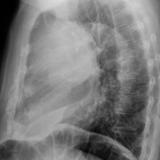

Case 9 Thymoma Lat

Date: 04/04/2010

Views: 3171